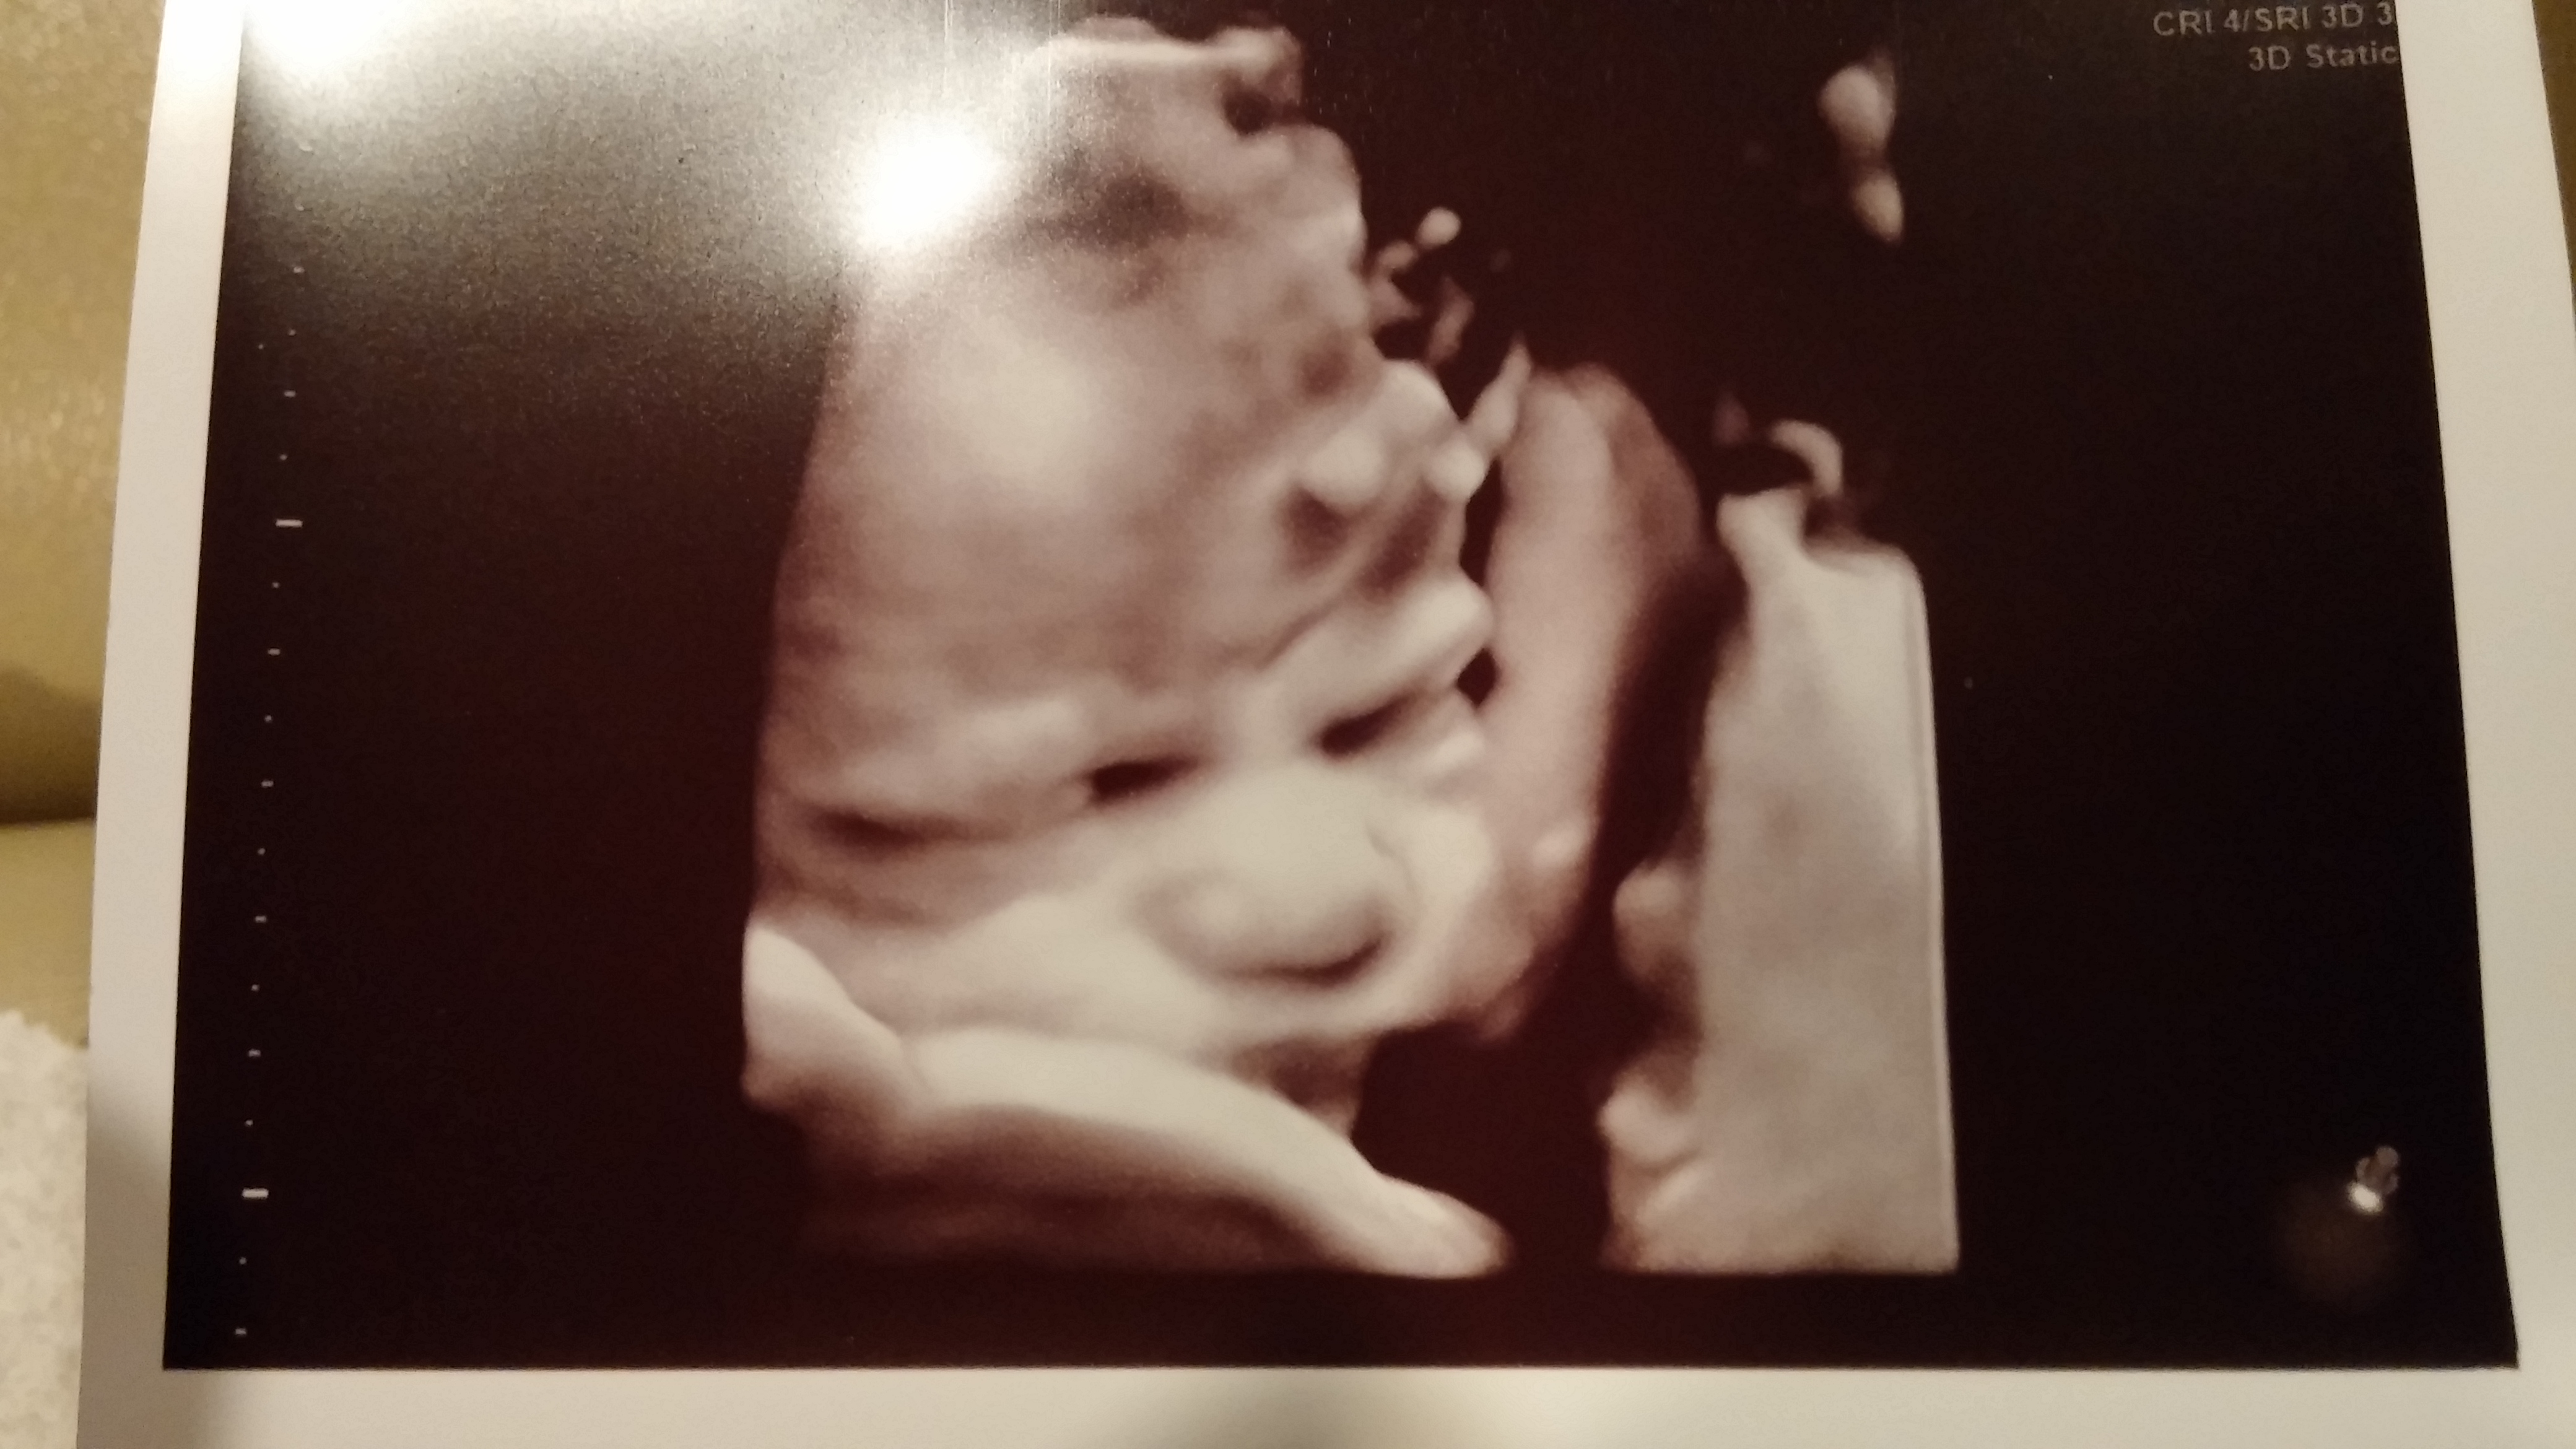

27 weeks and 4 days, and baby is growing perfectly in the 25th percentile. 2lbs 5oz and still team green! With GD, one of the things they worry about is growing a big baby. So I'm glad that this doesn't seem to be happening, at least not yet! Here's the perfect little face, "I will call him squishy, and he will be my squishy!" ~Dori, Finding Nemo

• Thanks! lol, it was the first thing that popped in my head when I saw this shot!